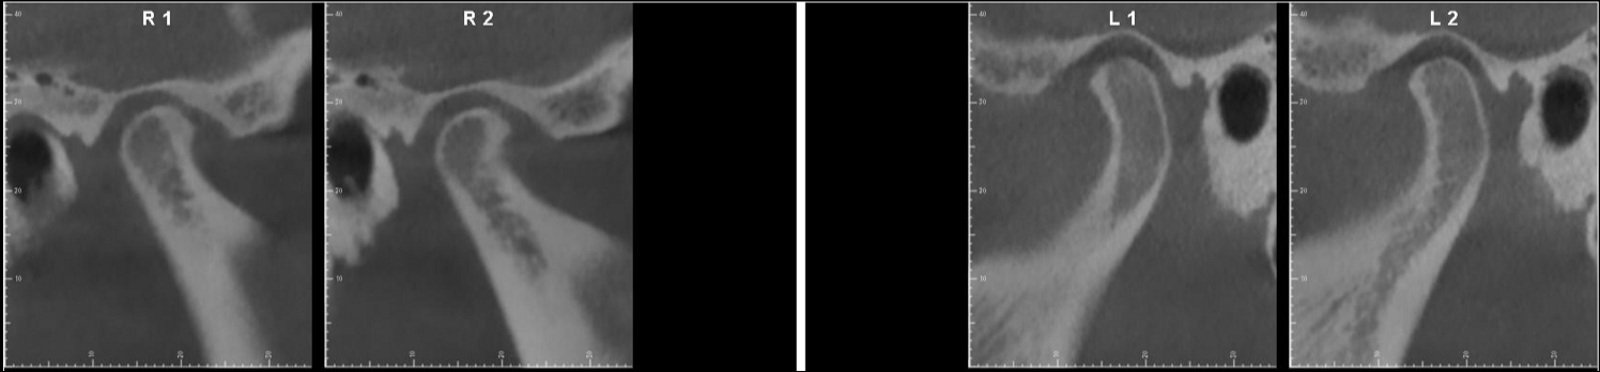

The panoramic radiograph showed slight bone loss, the presence of the maxillary third molars and mandibular left third molar and correct root morphology (Fig. 33). In the cephalometric radiograph and tracing, a Class II skeletal pattern and a marked negative torque of the maxillary incisors were observed (Fig. 34). The CBCT scan of the condyles showed that both condyles were well corticated, although the right condyle had undergone a process of PCR with reparation, evident from the good corticalisation and osteophyte (Fig. 35). This resorption process had affected the ramus, the right mandibular ramus being shorter than the left. This perfectly explained the reason for the patient’s mandibular deviation. We also observed a lack of functional space around the right condylar head, which was a clear sign that there was probably no disc present.